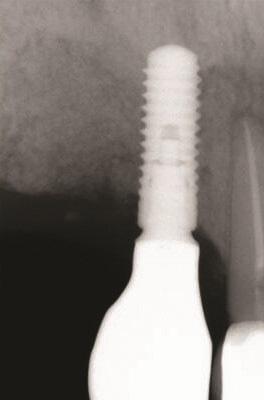

Пациент 1: Пациентка 30 лет с неосложненным медицинским анамнезом обратилась с имплантатом № 2.1, у которого диагностирован ретроградный периимплантит. Зуб № 2.1 был заменен имплантатом 8 лет назад из-за травмы в анамнезе и неудачного лечения корневых каналов. Имплантат демонстрировал периапикальную рентгенопрозрачность со свищевым ходом, ведущим к верхушке имплантата № 2.1 (Фото 1 и Фото 2). У пациентки была высокая линия улыбки с более длинными клиническими коронками зубов №№ 2.1 и 2.2 по сравнению с №№ 1.2 и 1.1 (Фото 1 и Фото 2).

Фото 1 и Фото 2. Случай 1: Первоначальная клиническая картина с гуттаперчевым штифтом, установленным в апикальный свищ зуба № 2.1 (Фото. 1); рентгеновский снимок, показывающий гуттаперчевый штифт, ведущий к периапикальному поражению (Фото. 2).